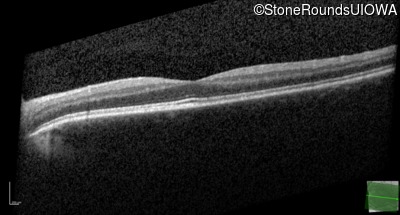

Age at visit: 17 years (Visit 2)

This 17 year old male had normal vision until about 6 months earlier when he began to lose central vision. The left eye may have been affected prior to the right eye.

Diagnosis & molecular findings

Leber Hereditary Optic Neuropathy MT-ND4 11778 A>G   MT